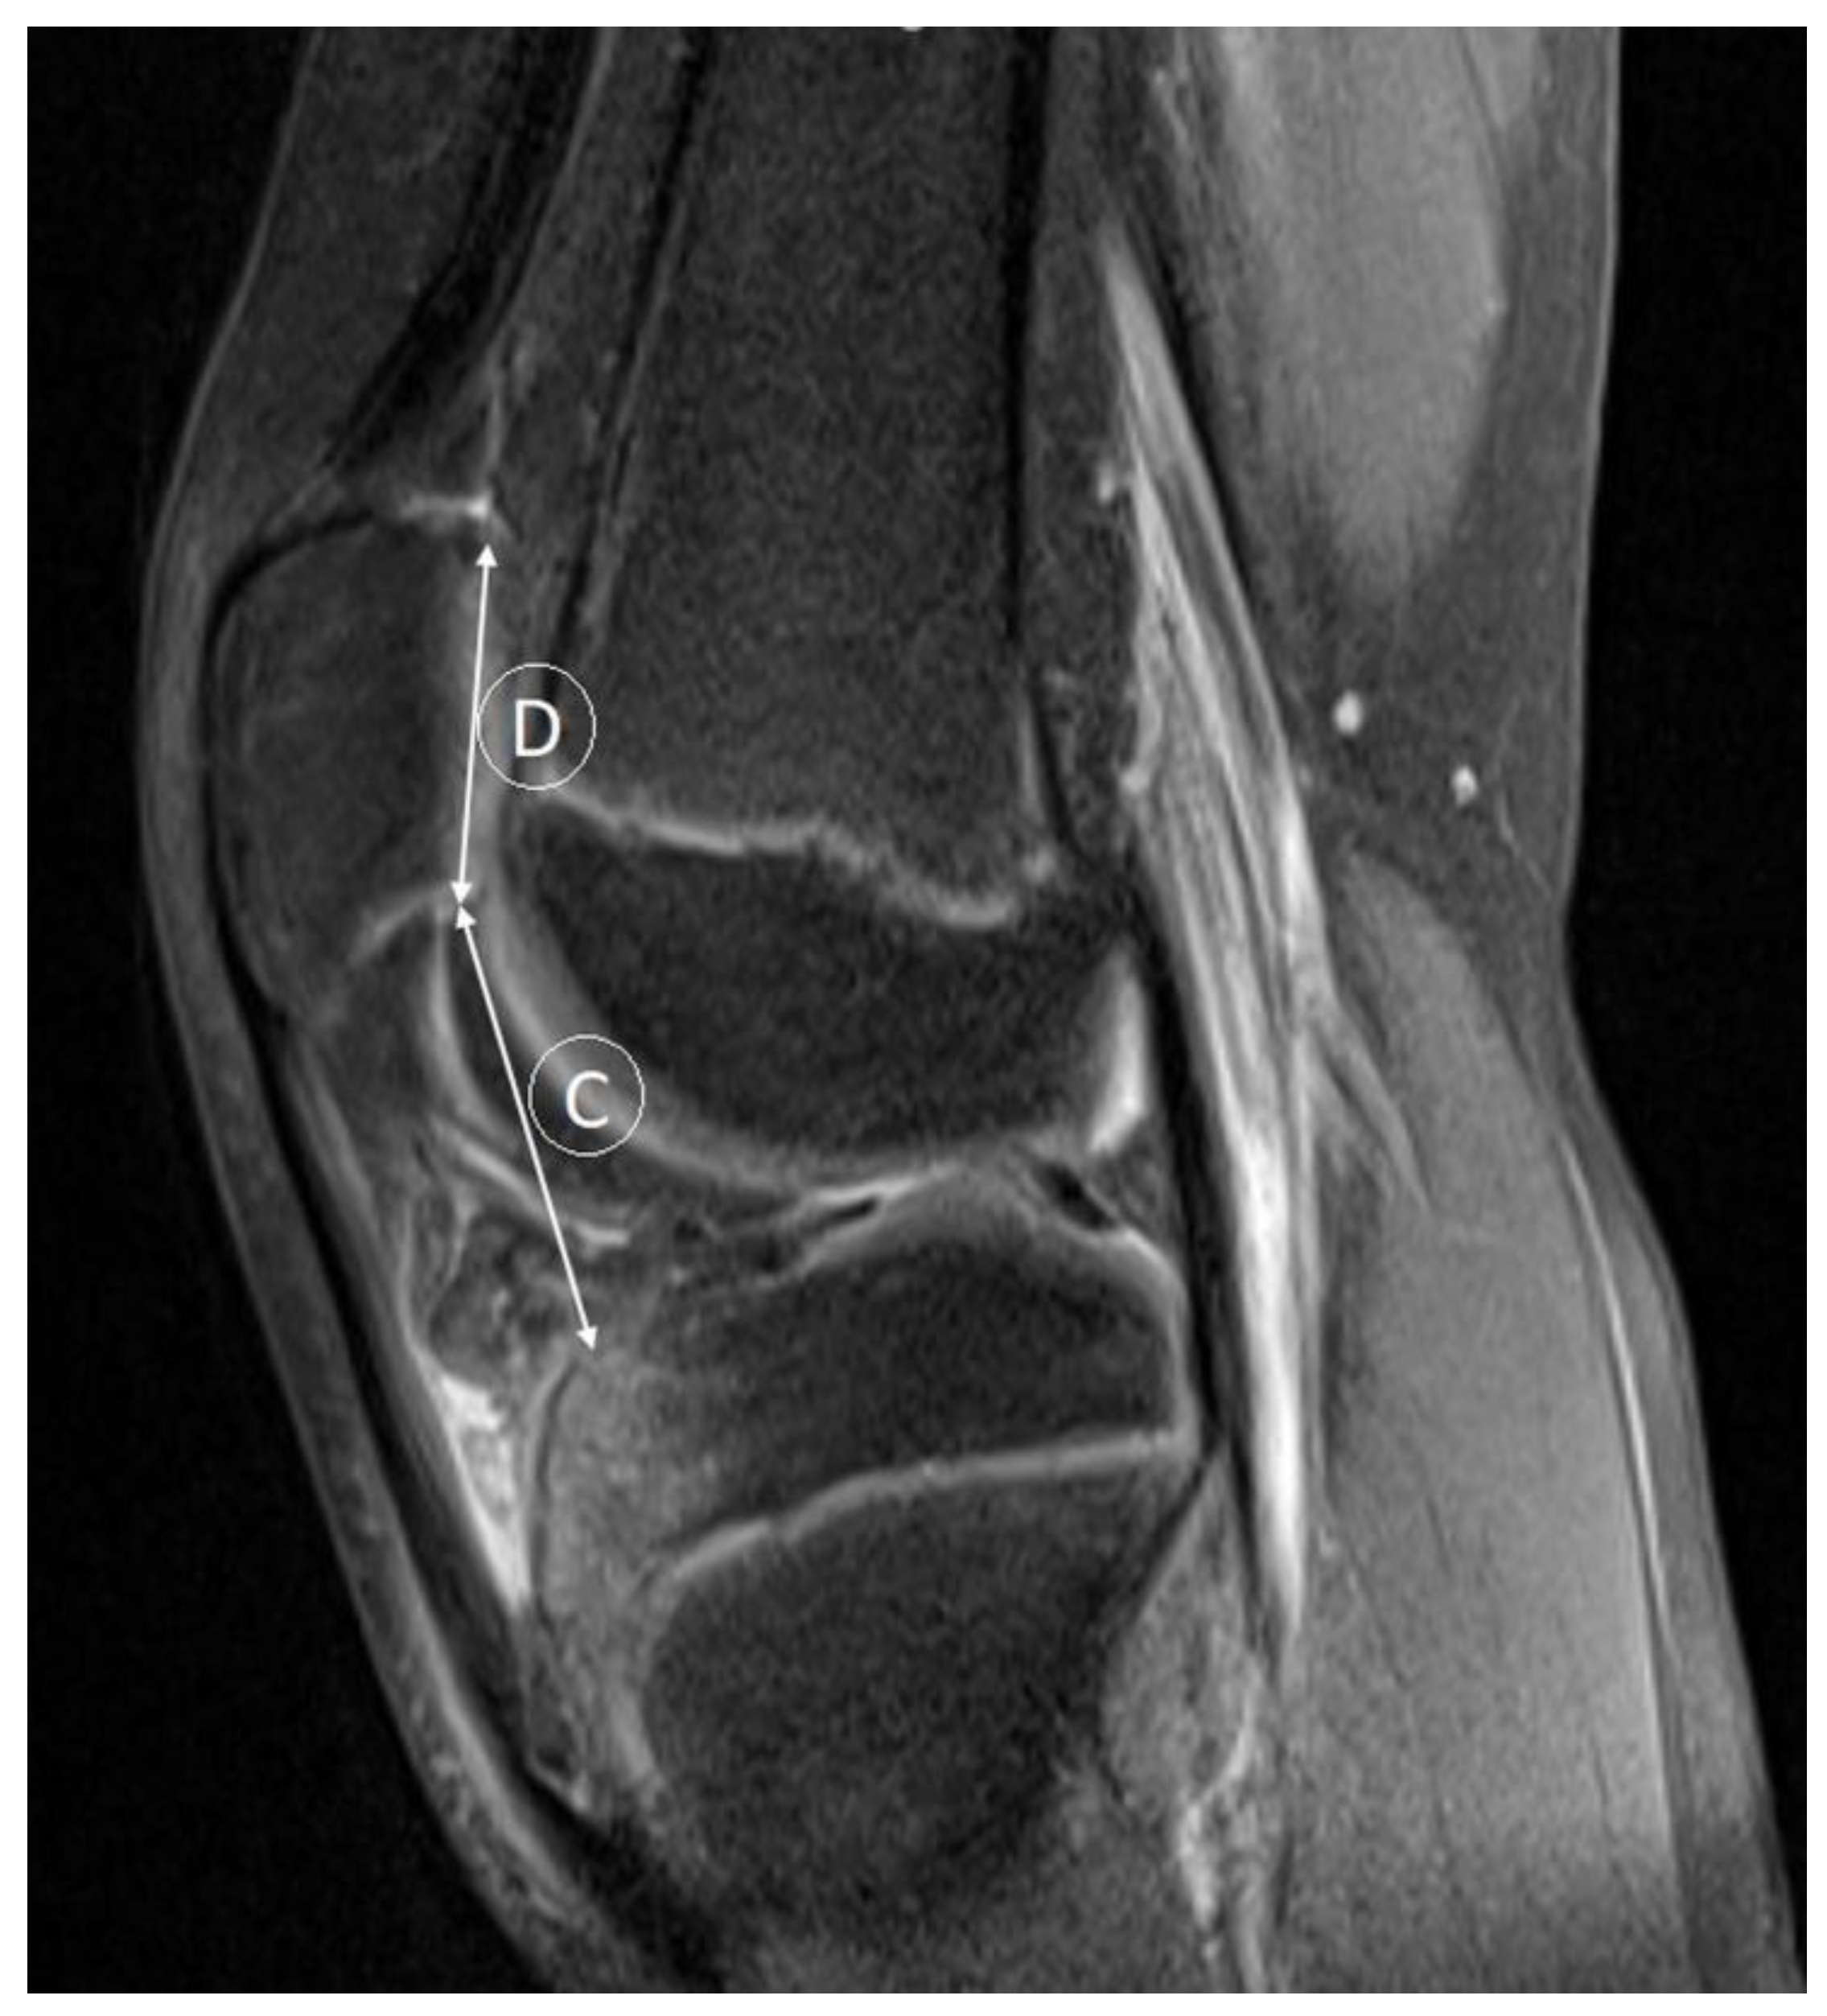

- Verhulst, F.V.; van Sambeeck, J.D.P.; Olthuis, G.S.; van der Ree, J.; Koeter, S. Patellar height measurements: Insall-Salvati ratio is most reliable method. Knee Surg. Sport. Traumatol. Arthrosc. 2020, 28, 869–875. [Google Scholar] [CrossRef] [PubMed]

- Kurowecki, D.; Shergill, R.; Cunningham, K.M.; Peterson, D.C.; Takrouri, H.S.R.; Habib, N.O.; Ainsworth, K.E. A comparison of sagittal MRI and lateral radiography in determining the Insall-Salvati ratio and diagnosing patella alta in the pediatric knee. Pediatr. Radiol. 2022, 52, 527–532. [Google Scholar] [CrossRef] [PubMed]

- Thévenin-Lemoine, C.; Ferrand, M.; Courvoisier, A.; Damsin, J.P.; Ducou le Pointe, H.; Vialle, R. Is the Caton-Deschamps index a valuable ratio to investigate patellar height in children? J. Bone Jt. Surg. 2011, 93, e35. [Google Scholar] [CrossRef] [PubMed]